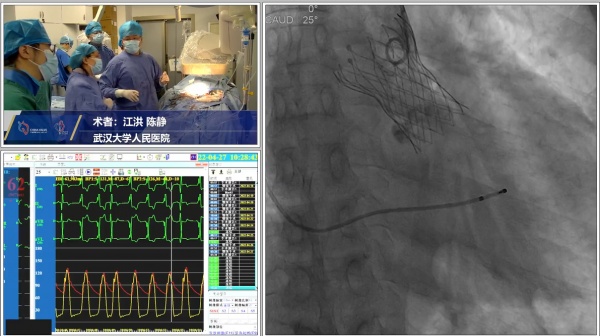

为邱老汉做手术的江洪教授和陈静教授,以及患者的影像图。

手术当天,专家团队仅用15分钟就为邱爹爹成功植入了VA-ECMO,术后即刻复查彩超显示,瓣膜原本的重度狭窄及关闭不全已得到完全解除,即刻射血分数提高8%。邱老汉的胸闷喘气症状当即得到了明显缓解。术后第二天,其心衰指标已从6万降到了3千。